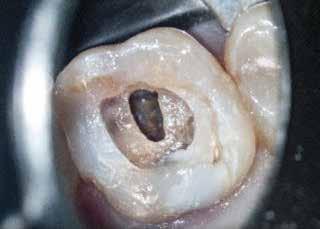

1. a–g. ábrák: A direkt pulpasapkázás lépései. Kiindulási bitewing-felvétel: A meglévő restaurátum közel helyezkedett el a pulpakamrához (a). Kiindulási periapicalis felvétel: Nincs periapicalis elváltozás fennállására utaló jel (b). A pulpaexpozíció (c). A vérzéscsillapítás céljából 20 másodpercen keresztül steril vattagombóccal történő kompressziót követően látható pulpaseb (d). A pulpasapkázás céljából behelyezett anyag, a széli részek tisztázása előtt készült felvétel (e). A röntgenárnyékot nem adó ideiglenes tömés behelyezése után készült felvétel (f). Az első ülés végén a röntgenárnyékot nem adó ideiglenes töméssel ellátott fogról készített röntgenfelvétel (g).

Direkt pulpasapkázás

Ha a kialakult pulpasebek ellátatlanul maradnak, először irreverzibilis pulpitis, majd pulpanecrosis fog bekövetkezni.7 Ennek megfelelően amennyiben a beavatkozásokat végző orvos nem kívánja a még élő pulpát eltávolítani (pulpectomia, exstirpáció), úgy a direkt pulpasapkázás számít a megfelelő terápiás választásnak. Ez különösen igaz a fiatal páciensek maradó fogainak esetében.8 A jelenleg elérhető – főleg sűrű konzisztenciájú – biokerámiák alkalmasak az ez

irányú felhasználásra. Ezek az anyagok azáltal képesek a dentinhez kötődni, hogy felszínen egy új hidroxilapatit réteget alakítanak ki. Ez annak köszönhetően, hogy az exponálódott pulpasebek közelében serkenteni tudják a sejtek toborzását és differenciálódását.9 Az MTA-hoz hasonló antibakteriális tulajdonságokkal is rendelkeznek a főbb kariogén baktériumokkal szemben (Streptococcus mutans, lactobacillusokkal),10 továbbá megfelelő a biokompatibilitásuk, és képesek reparatív dentinhidak képződését előidézni.

Esetbemutatás (1.)

Egy 35-éves férfi beteg akut ellátás céljából kereste fel rendelőnket. A jobb felső második kisőrlő (15) fogát érő hideg inge-

rekre jelentkező, rövid ideig tartó éles fájdalomra panaszkodott.

A diagnózisunk reverzibilis pulpitis volt. Periapicalis elváltozás jelenlétét nem vélelmeztük. A fogban lévő amalgámtömés eltávolítása során körülbelül egy 3 mm átmérőjű pulpaseb keletkezett a buccalis pulpaszarvnak megfelelően (1. a–g. ábrák) Mivel nem tapasztaltunk jelentős vérzést, és a diagnózisunk reverzibils pulpitis volt, ezért a direkt pulpasapkázás elvégzése mellett döntöttünk.

A kavitást 2,5%-os nátrium-hipoklorit oldattal fertőtlenítettük, majd sűrű konzisztenciájú kalcium-szilikát alapú anyagot (CeraPutty, Meta Biomed) készítettünk elő a direkt pulpasapkázás elvégzéséhez. Az első kezelés végén röntgenárnyékot nem adó ideiglenes töméssel (NexTemp LC, Meta Biomed) zártuk

az üreget annak érdekében, hogy a direkt pulpasapkázásra használt anyag megfelelő pozícióját radiológiailag ellenőrizni tudjuk. A második ülés során kompozit tömőanyagból (Ezfil, Meta Biomed) direkt adhezív restaurátumot készítettünk.

A kezelést követően a beteg tünetmentes volt. A kérdéses fog a kontrollvizsgálatok során végzett szenzibilitástesztekre fiziológiás reakciókat adott. A hat hónapos kontroll alkalmával készített röntgenfelvételen a sérülésnek megfelelően széles dentinhidat észleltünk (2. ábra). A restaurátum a hároméves kontroll során is megfelelőnek bizonyult (3. ábra)